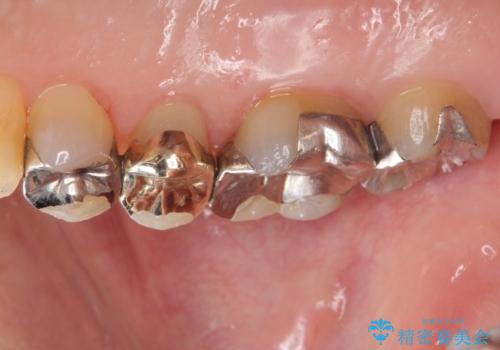

歯が欠けた 金属による割れない修復

- 詰め物が欠けたとのことで来院されました。

実際は詰め物ではなく歯自体が欠けている状態でした。

銀の詰め物を外し、欠けたところを覆うように新しい詰め物を作成します。

欠けたところに金属を使用することで、再度欠けてしまうリスクを抑えました。